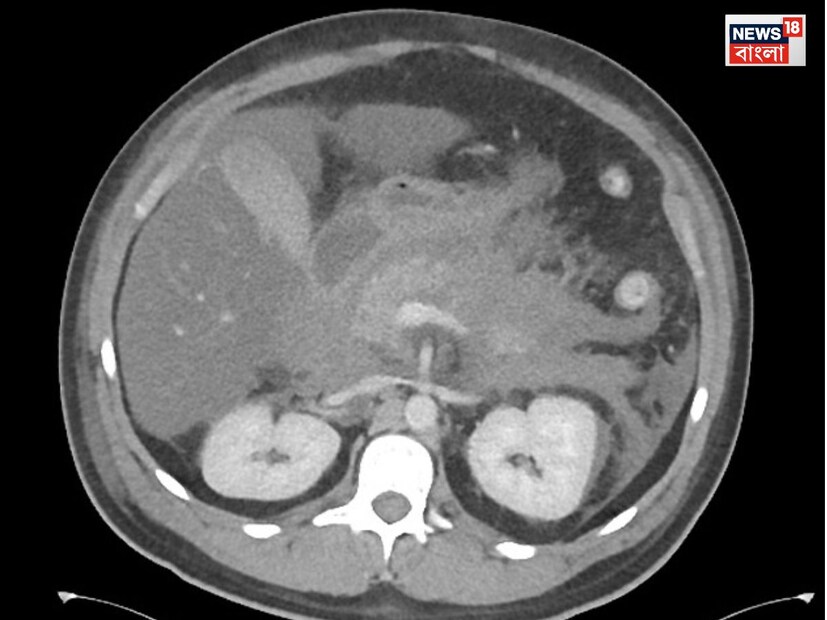

Hemorrhagic Pancreatitis: ময়নাতদন্তের প্রাথমিক রিপোর্টে চিকিৎসকরা বলছেন, অ্যাকিউট হেমরেজিক প্যানক্রিয়াটাইটিস ছিল তাঁর। এছাড়া ময়নাতদন্তে চিকিৎসকরা দেখেছেন, সৃঞ্জয়ের হার্টের আকার স্বাভাবিকের চেয়ে বেশি। কিডনি ও লিভারের আকারও স্বাভাবিকের চেয়ে বেশি ছিল।